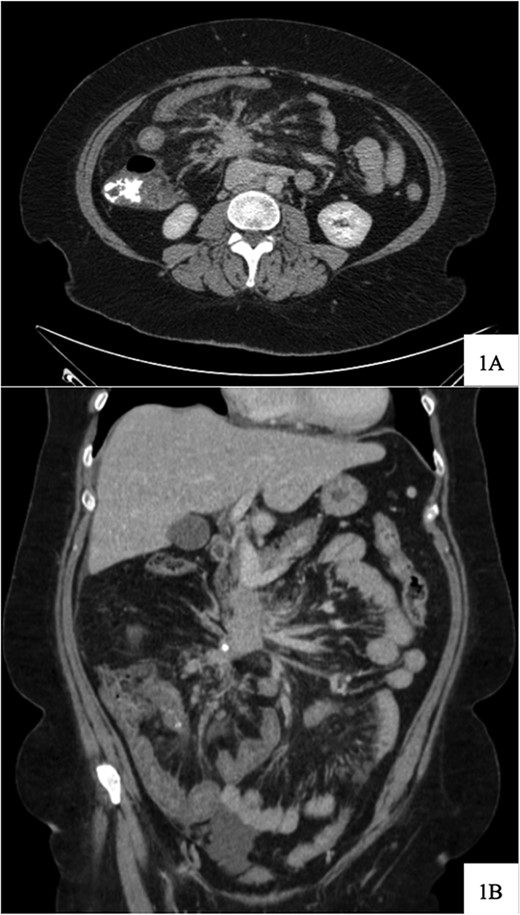

Regarding her oncologic history, she was diagnosed with NET in October of 2017 when a computed tomography (CT) scan performed for intermittent abdominal cramping and diarrhea revealed a mass near the third portion of the duodenum and the root of the mesentery (Fig. 1). Biopsy of the mass revealed a well-differentiated NET. Further work-up with DOTATATE positron emission tomography (PET)/CT revealed a small bowel primary likely emanating from the terminal ileum as well as multiple lesions in the neck, chest, and liver (Figs 2 and 3). The periduodenal mass intimately involved the root of the mesentery, SMA, and SMV. She was initially treated with Lanreotide for many years with close monitoring and later underwent systemic treatment with Lutathera, a Peptide Receptor Radionuclide Therapy, from April 2020 to November 2020. She subsequently resumed Lanreotide in December of 2020, which she was on at the time of admission. Her disease remained largely stable on imaging over the next three years; however, her symptoms had been worsening over the few months leading up to her presentation.

Computed tomography scan at time of diagnosis in September 2017 revealed a mass near the third portion of the duodenum and the root of the mesentery in the axial (A) and coronal (B) views.